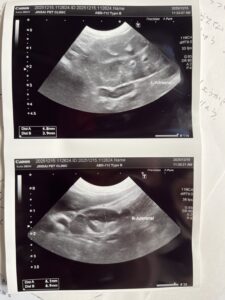

チャチャちゃん 結果

⭕️肺腫瘍 相変わらず大きい

⭕️胆石あり ⭕️中性脂肪高い

⭕️左脚 歩行時傾き 立ち上がり弱い

馬尾症候群

⭕️腰椎 1と2異常

⭕️肘たこ 良性

⭕️顔面チック症

2025年 年内で検診出来ました。